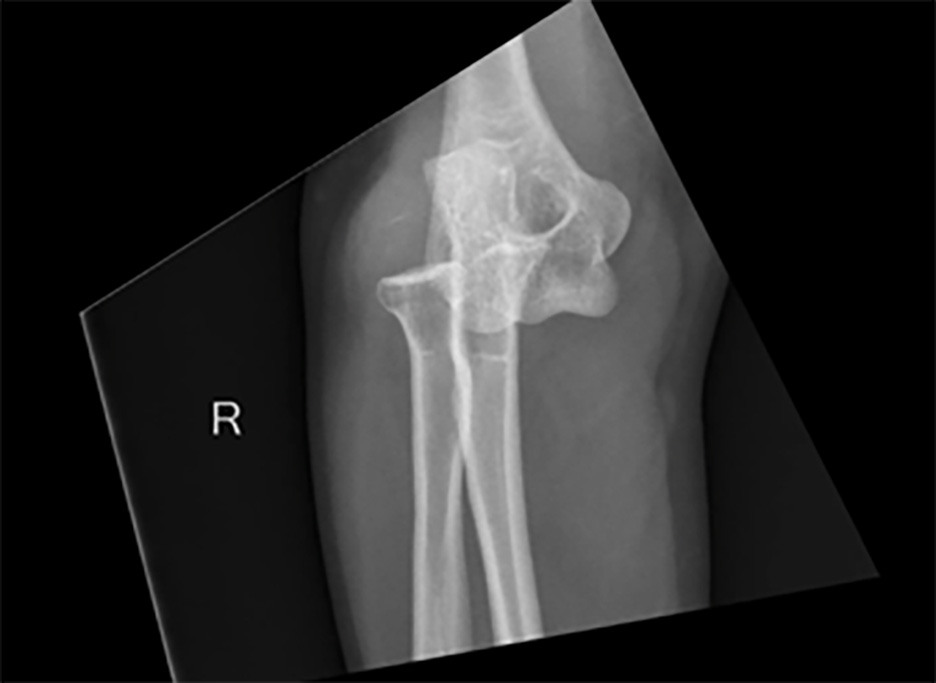

Elbow Dislocation

Elbow dislocations are the most common pediatric major joint dislocations and the second most common dislocations in adults. The mechanism typically involves a FOOSH resulting in a posterior dislocation.27 A thorough neurovascular examination is warranted given the proximity of the brachial artery, ulnar nerve, and median nerve; these injuries less commonly involve the radial nerve.27 X-ray is the preferred imaging modality (see Figures 3 and 4), with CT imaging considered for complex injuries involving surgical planning.28 After neurovascular assessment and imaging confirms the diagnosis, expedited reduction is indicated. Various reduction techniques are summarized in Table 2 and include:

Figure 4. Posterior Elbow Dislocation on AP View |

![]() |

AP: anteroposterior Image courtesy of Hunter Roberts, MD. |